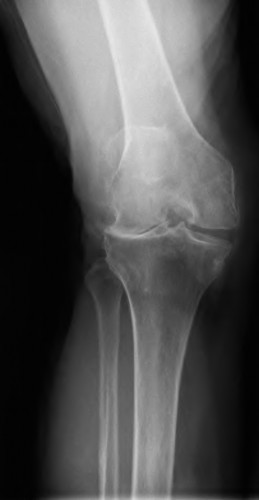

A 72-year-old female presents with progressive left thigh and knee pain for the last year. 5 years ago she sustained a femoral neck fracture treated with the implant seen in Figures A-C (current radiographs). The thigh pain is worse with weight-bearing. C-reactive

protein and erythrocyte sedimentation levels are within defined limits. Which of the following is the most likely cause of her pain?